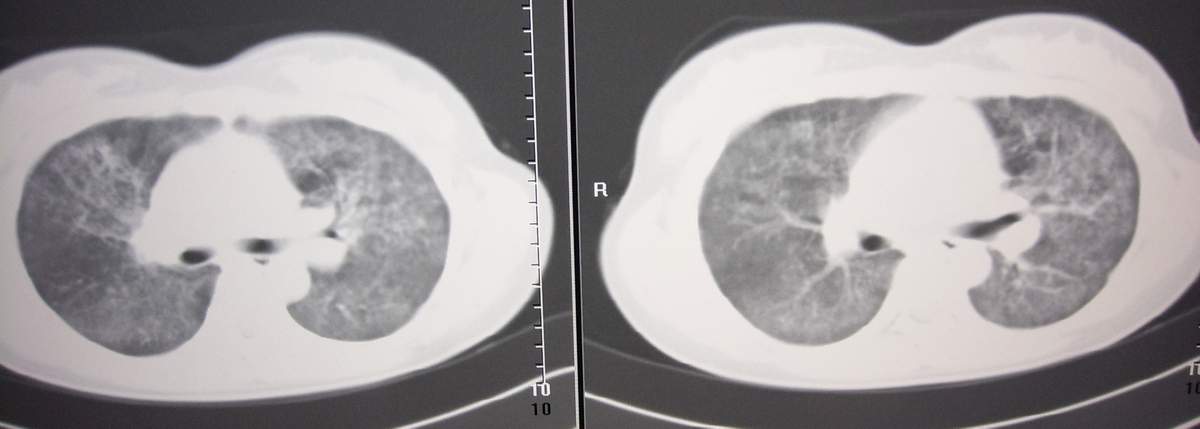

标题: CT7371:[讨论]肺部病变!

女,咳嗽、气喘2月余。

双肺纹理增多,紊乱,呈网格状,期间搀杂斑片及磨玻璃样阴影.考虑;感染性病变_首先考虑:特殊感染:嗜酸性肺病.

双肺弥漫磨玻璃样影,边界不清,似蝶翼征。肺纹理增多。

考虑:肺泡蛋白沉积症。建议临床进一步检查。